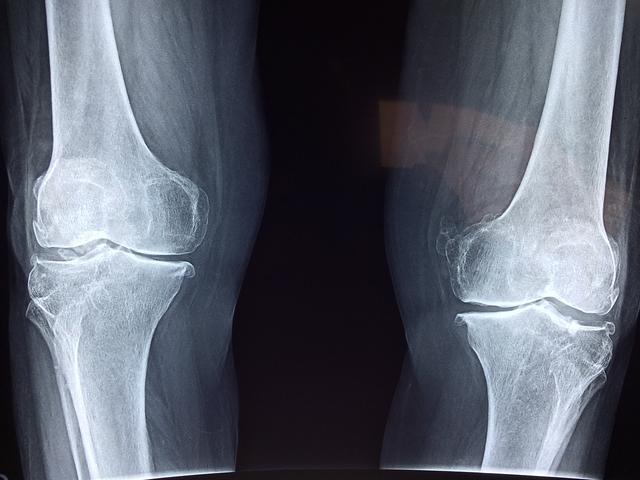

অস্টিও মানে হাড়, আর পরোসিস মানে ছিদ্র হওয়া। অর্থাৎ, ছিদ্রযুক্ত হাড়ের সমস্যাই হলো অস্টিওপরোসিস। এই রোগে হাড়ের ঘনত্ব কমে পাতলা হয়ে যায়। এতে শরীরের হাড়ের ভেতরের গঠন দুর্বল হয়ে যায়। এর ফলে হালকা আঘাতে হাড় ভেঙে যাওয়ার আশঙ্কাও থাকে।

চিকিৎসকদের মতে, হাড়ক্ষয়ের ঝুঁকি বাড়ে বয়স বেশি হলে । অনেক সময় ফ্র্যাকচার হলে এই রোগ ধরা পড়ে। তবে কিছু কিছু ক্ষেত্রে ঘাড়ে ও কোমরে শিরদাড়ায় প্রতিনিয়ত ব্যথা করলে ধরা পড়ে।